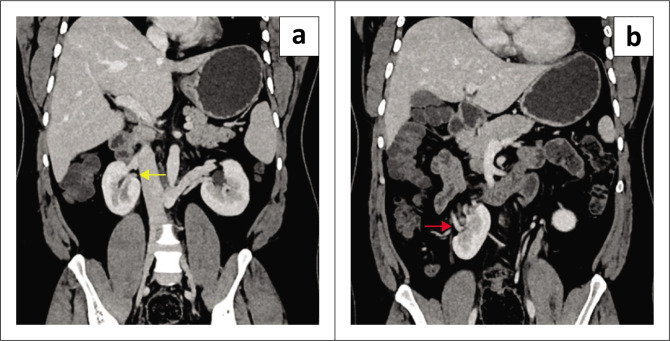

Supernumerary kidney (SK) is an uncommon anomaly of the urinary tract, usually occurring on the left side. A rare case of a partially-fused, SK on the right side is presented. The diagnosis is made through the identification of a distinct pelvicalyceal system along with its supplying renal artery and vein, utilising ultrasound, CT, or MRI.

Contribution: Correct diagnosis of partially-fused, supernumerary kidneys based on imaging is crucial to avoid unnecessary procedures, so that asymptomatic cases are managed conservatively.